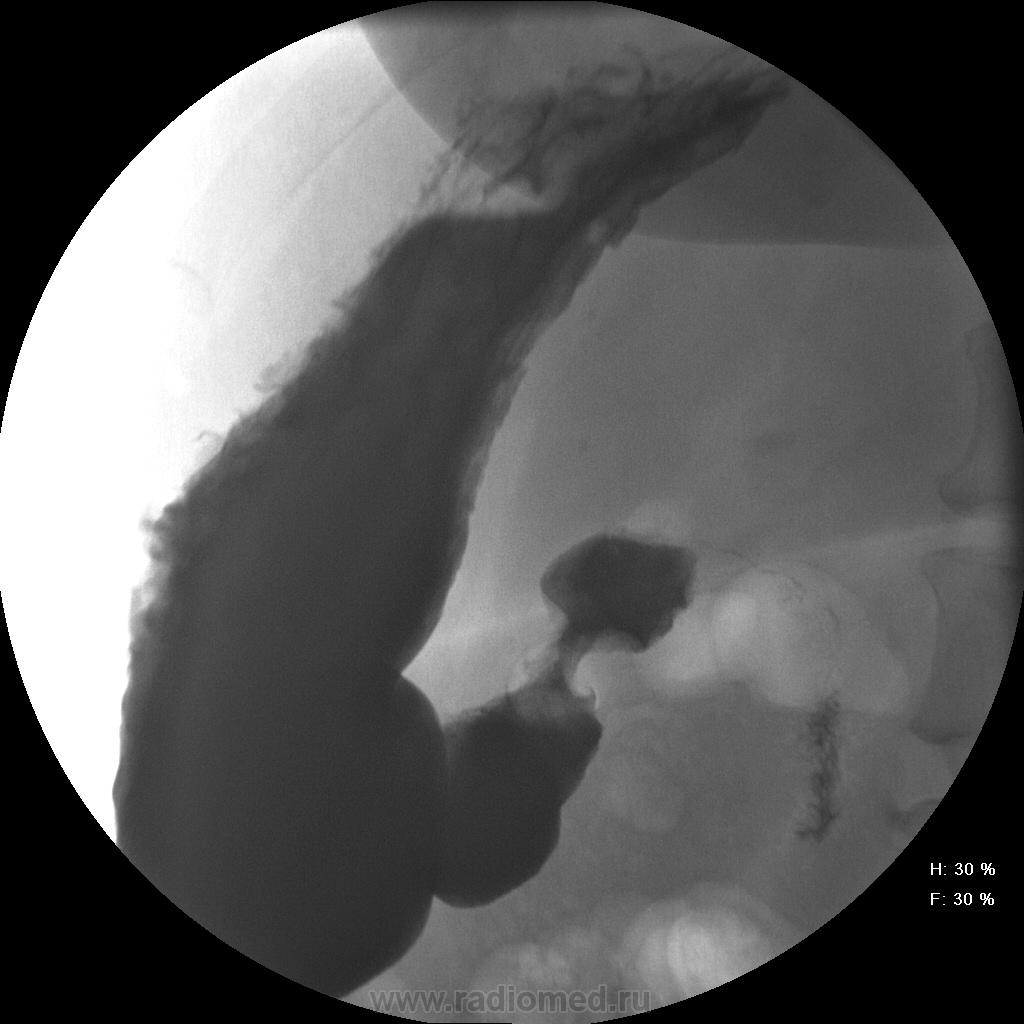

Женищина 49 лет, повышенного питания, обратилась с жалобами на потерю аппетита, жжение после чуть острой пищи, отрыжку с неприятным запахом, иногда темный стул, несколько похудела. Данные жалобы с сентебря-октября. Никуда не обращалась, коррегировала питанием. В последнее время стало хуже, обратилась...

Привратник удлиннен и ригиден, такое бывает при раке. Рек. ЭГДС.

Вы правы. я несколько недорасказал. женщина пришла уже с фгдс - инфильтративно-язвенный процесс в выходном отеде желудка у привратника по малой кривизне с переходом на переднюю стенку. так что прицельно смотрел этот отдел. перистальтка была ослаблена, краевой дефект в препилорической зоне по малой кривизне, передней стенке, кажущееся удлинение привратника, нависание основания луковицы - вообщем как в книжке. эвакуация было не изменена. написал рак выходного отдела желудка. вчера пришла гистология - высокодиф-я аденокарцинома. вот такая история.

Пока, касаясь только луковицы, но не препилорического отдела. "Ниши" в луковице есть, и они нуждаются в объяснении.

Конечно, в пилорическом канале уже растет, и "это" растет, уже и препилорической части и в луковице 12-ти перстной кишки.

А на фоне "этого" растет уже "изъязвления"?